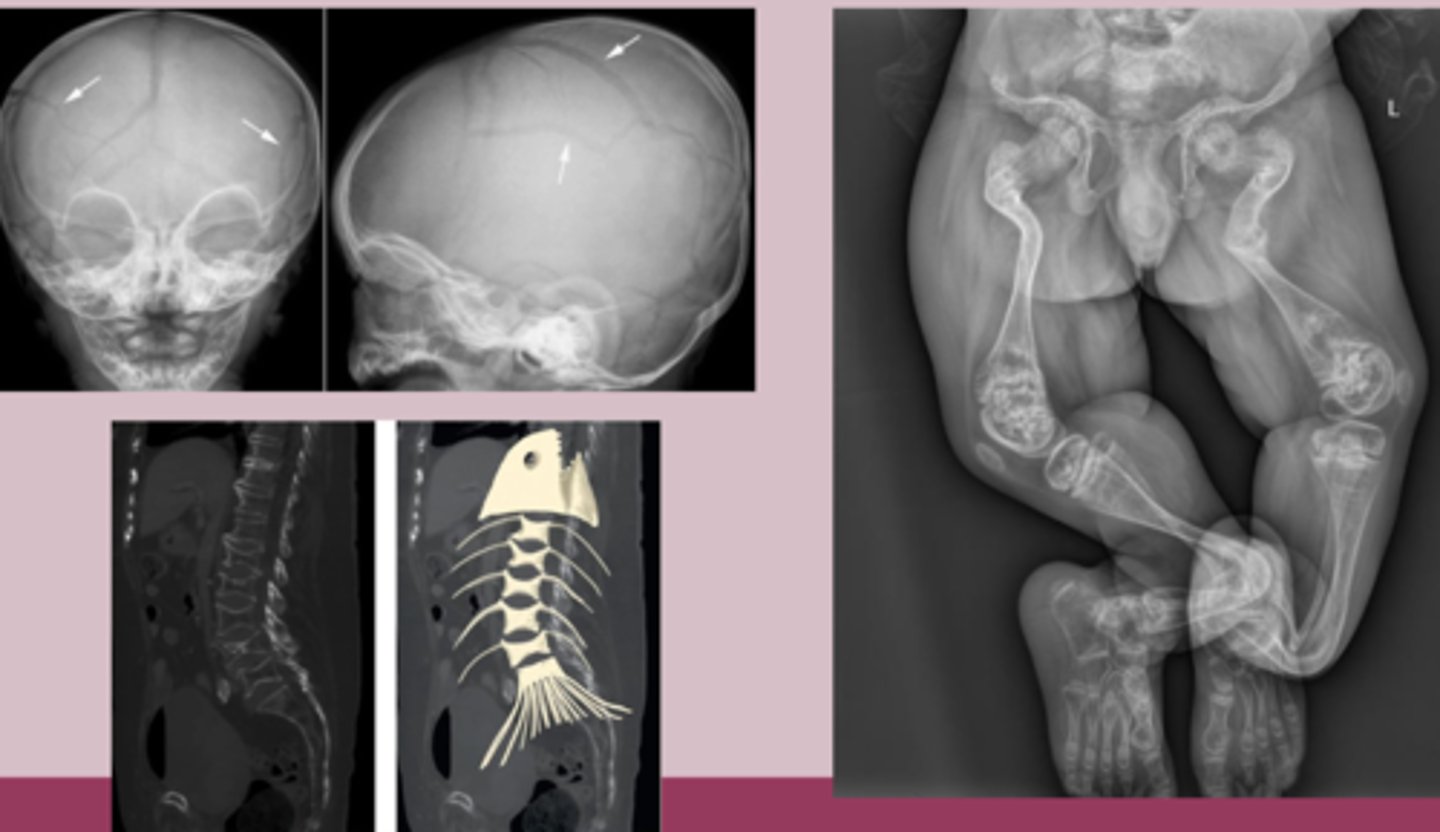

osteogenesis imperfecta sx

-multiple fractures throughout life with minimal or no trauma

-bone pain

-short stature and growth delay

-easy bruiding, excessive sweating

-dental problems

-blue or gray sclera

-bone deformities, hearing loss, triangular facies

-type 1: normal stature, blue sclera, hearing loss

osteogenesis imperfecta dx

-clinical

Imaging

-Xray: generalized osteopenia, multiple fractures, thin cortices, bowing deformities, codfish vertebrae

-DEXA scan: show decreased BMD